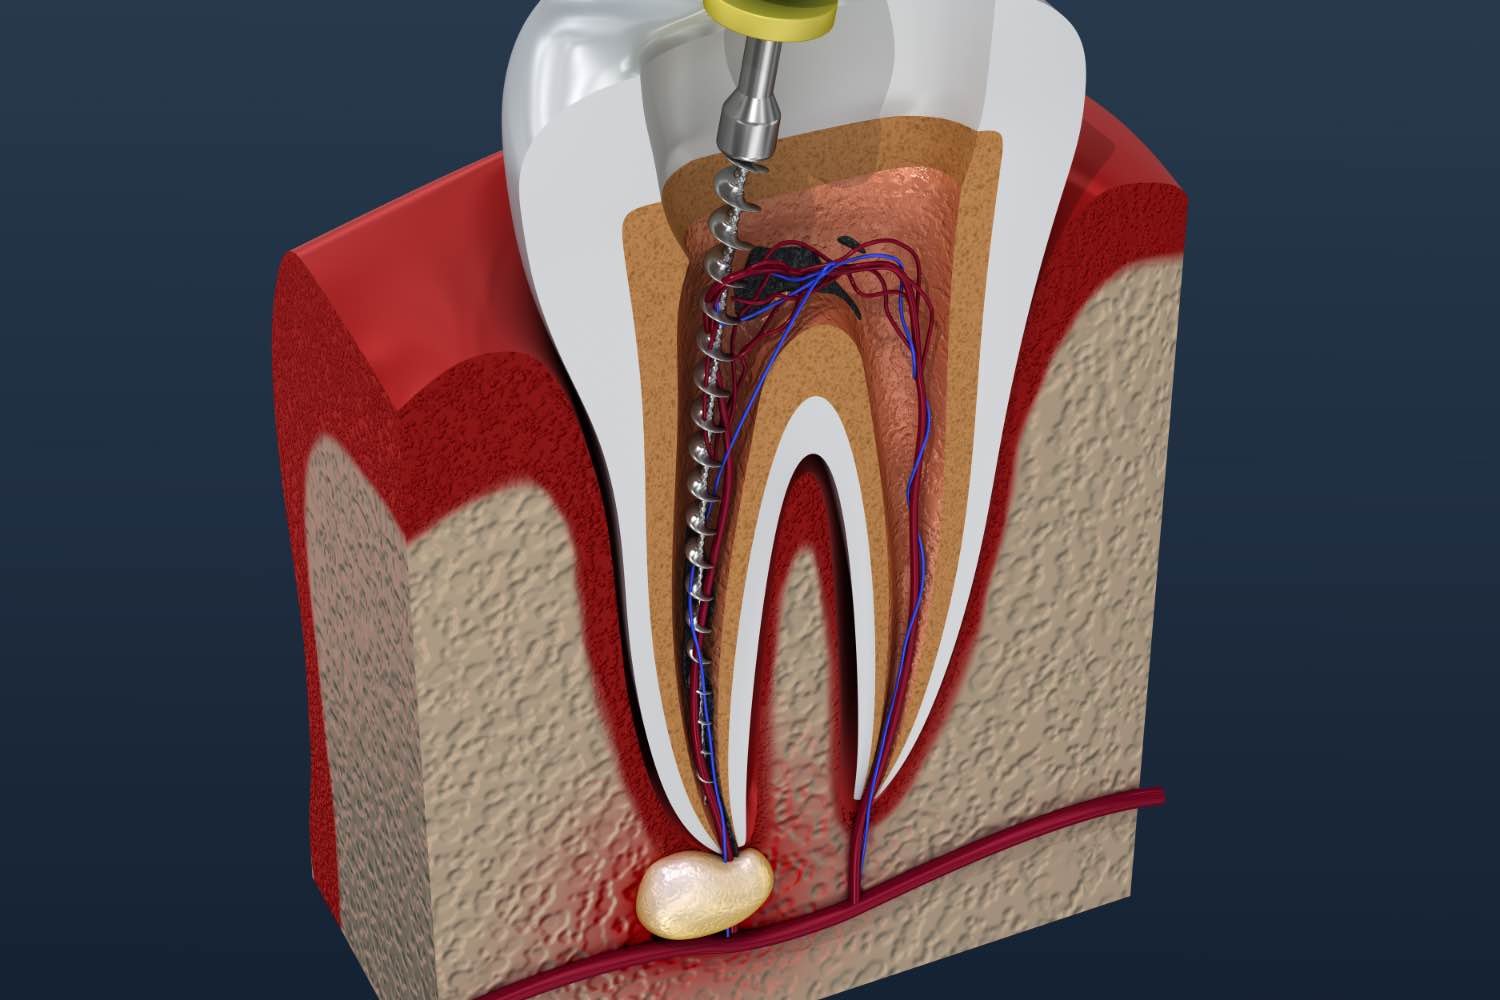

Root Canal

A root canal removes infected tooth pulp, cleans the canals, and seals them to prevent infection.

Root Canal

A root canal is a dental procedure used to treat infection or damage inside a tooth. It involves removing the infected pulp, cleaning and disinfecting the root canals, then sealing them to prevent further infection. This treatment helps save the natural tooth, relieve pain, and restore normal chewing and appearance.